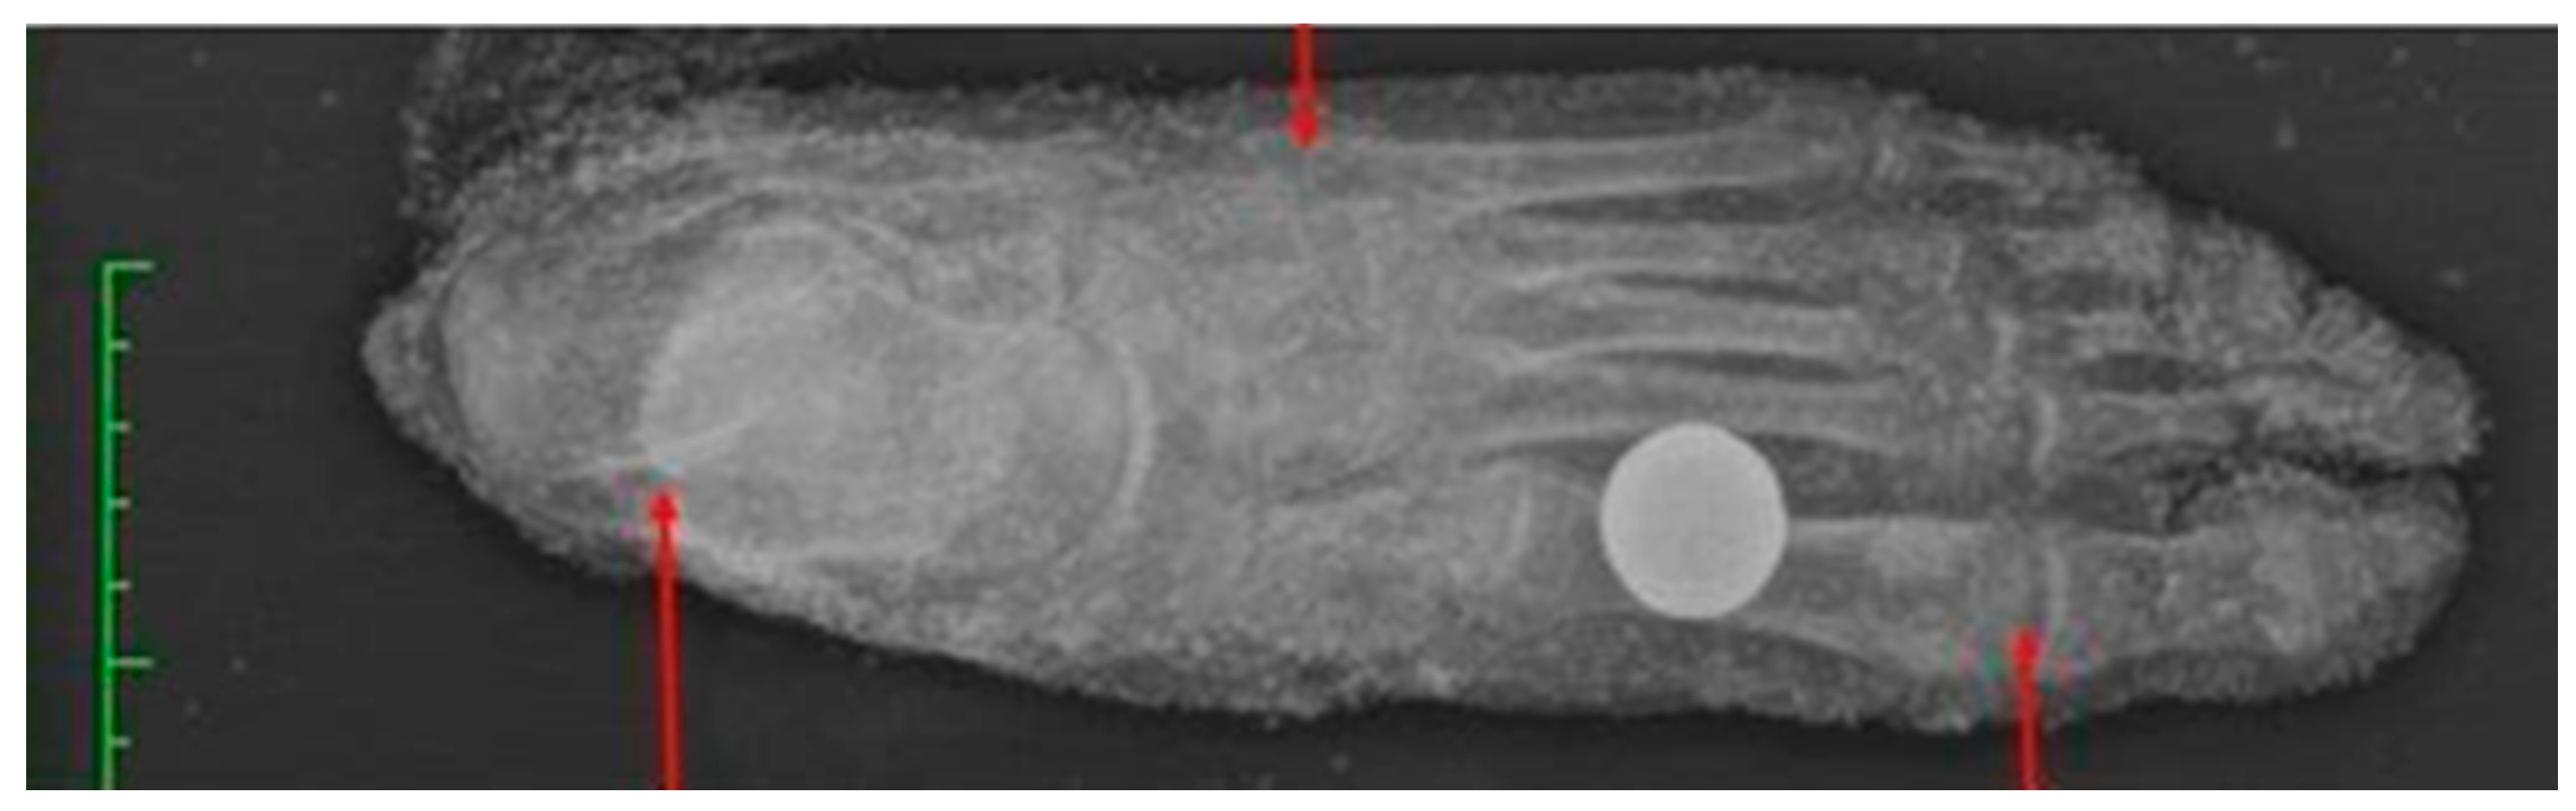

With regard to the anthropometric investigation of the isolated foot, Case B, only metric and morphological methods were applied, based on radiographic-digital investigation through the use of the Horos software (version 3.3.6, Horos Project, Annapolis, MD, USA) that allowed the digital extrapolation of metric measurements to be conducted (Figure 7) [21].

For the determination of sex, the method of discriminant analysis applied to the relative measurements of the calcaneus was applied [22]. For the determination of age, the ossification centres of the nuclei of the calcaneus, talus, metatarsals and phalanges were analysed [13]. For the determination of stature, a formula applied only to the maximum plantar length was used [23].

Figure 7. Analysis of the degree of fusion of ossification nuclei of the isolated foot on radiography.